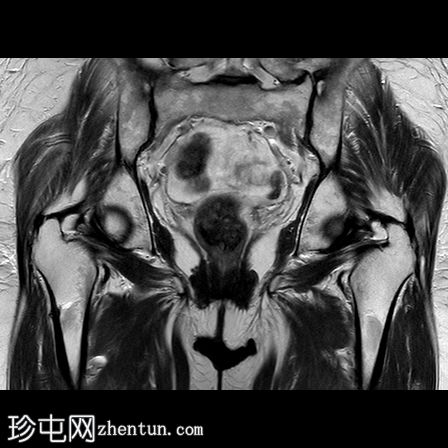

MRI

冠状位

T1

一条水平T1和T2低信号骨折线横断右股骨干外侧皮质。近1/3的骨干周长受累,并伴有邻近骨髓水肿。其余皮质骨完整。左股骨未见异常。